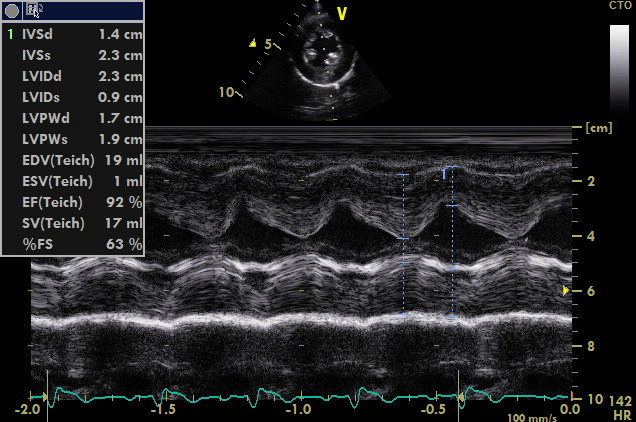

Cucciolo femmina di Rottweiler 60 gg di eta’ soffio di forte intensita’ sistolico ascultabile in tutti i quadranti ,meglio nel IIo spazio intercostale a destra dello sterno. ,polso di difficile rilievo piccolo e celere,ritardato accrescimento rispetto ai fratelli, battiti ectopici, nessuna sintomatologia sincopale evidenziata.

come si puo’ notare dai particolari nelle immagini zoom la struttura valvolare appare integra con una normale conformazione delle cuspidi la turbolenza e’ generata da una piccola banda fibrosa sottovalvolare ,in questo caso a dispetto delle alterazioni minime visualizzabili nell’esame B mode la stenosi sulla base del gradiente appare severa ,il PHT inferiore ai 300mm/sec dell’insufficienza aortica che quasi sempre accompagna la stenosi indica pressioni diastoliche nel ventricolo sx elevate

I difetti possono coesistere in questo caso la polmonare e’ normale ,nei primi video si ha la sensazione che coesista un DIV (flusso in avvicinamento concomitante la sistole tuttavia le differenze di gradiente sono troppo elevate tra camera destra e sx dovrebbe generarsi turbolenza che non si vede ,il soggetto deve essere comunque ricontrollato .

– Classe 3: la proliferazione endocardica sottovalvolare forma un restringimento di tutto il tratto di efflusso in senso circonferenziale e per tutta la sua lunghezza. Questa lesione, in ecocardiografia, viene classificata come stenosi subaortica a tipo tunnel (tipo 3).Seguendo la classificazione di Pyle la morfologia di questo caso non appare inquadrabile del tutto in quanto non si visualizzano noduli e neanche un ispessimento fibroso che riveste “quasi del tutto” il tratto di efflusso ,il cercine appare limitato al tratto prevalvolare .Bisogna considerare che la stenosi sub-aortica e aortica sono propagate nelle razze e nelle famiglie con base genetica; tuttavia non si conoscono completamente le modalità di trasmissione. Possiamo dire che non è propriamente una malattia congenita perché le lesioni possono non essere presenti alla nascita o, in qualunque caso, non completamente sviluppate. Per questo motivo, una stadiazione clinica non deve essere effettuata prima degli 8-12 mesi di età.